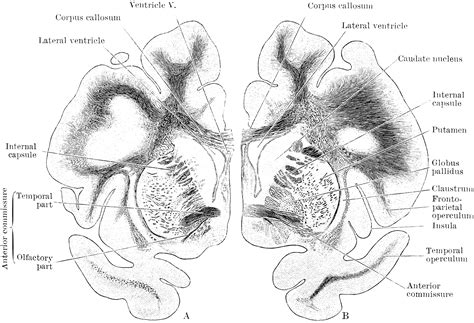

The coronal view of the brain is a vertical slice that divides the brain into front and back sections. This view is particularly useful for visualizing the brain's internal structures, such as the ventricles, the corpus callosum, and various lobes. By examining the brain in this orientation, neurologists and researchers can gain a deeper understanding of how different regions of the brain interact and function.

Key Structures Visible in the Coronal View

The coronal view reveals several key structures within the brain. Some of the most important ones include:

• Ventricles: These are fluid-filled cavities within the brain that help cushion and protect it. The lateral ventricles, third ventricle, and fourth ventricle are all visible in the coronal view.

• Corpus Callosum: This is a thick band of nerve fibers that connects the left and right hemispheres of the brain, facilitating communication between them.

• Lobes of the Brain: The frontal, parietal, temporal, and occipital lobes can be clearly seen in the coronal view, each responsible for different functions such as motor control, sensory processing, language, and vision.